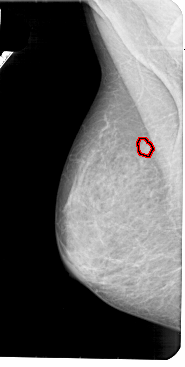

A_1947_1.LEFT_MLO

LEFT_MLO LINES 5491 PIXELS_PER_LINE 2761 BITS_PER_PIXEL 12 RESOLUTION 43.5 OVERLAY

FILE: A_1947_1.LEFT_MLO.OVERLAY

TOTAL_ABNORMALITIES 1

ABNORMALITY 1

LESION_TYPE MASS SHAPE ROUND MARGINS CIRCUMSCRIBED

ASSESSMENT 3

SUBTLETY 4

PATHOLOGY BENIGN

TOTAL_OUTLINES 1

BOUNDARY